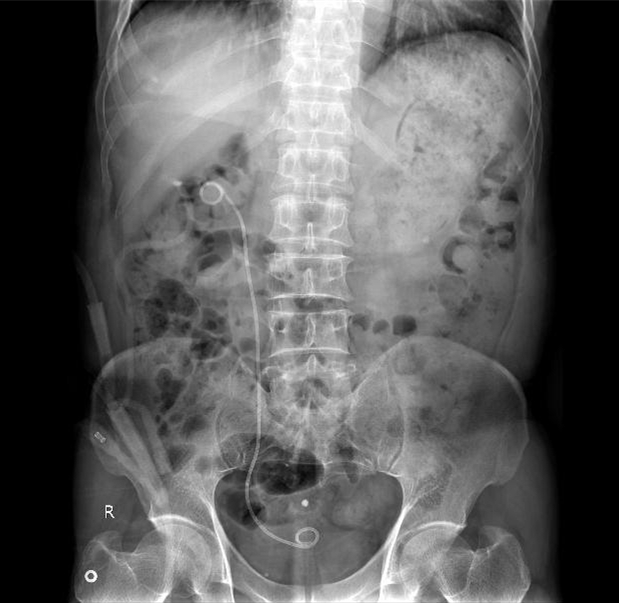

一期手术后右肾铸型结石清除干净

在经过精心准备后,以杨科主任、郑珏副主任医师为主的医护团队,在术前通过B超精准定位,术中运用“两步法”经过肾盏穹窿顶穿刺,完美的避开了肾窦内大血管,准确的建立起了超微通道。后开放钬激光迅速有效的碎石,结石经过铅笔孔样的碎石通道顺利冲出。一期手术顺利结束。